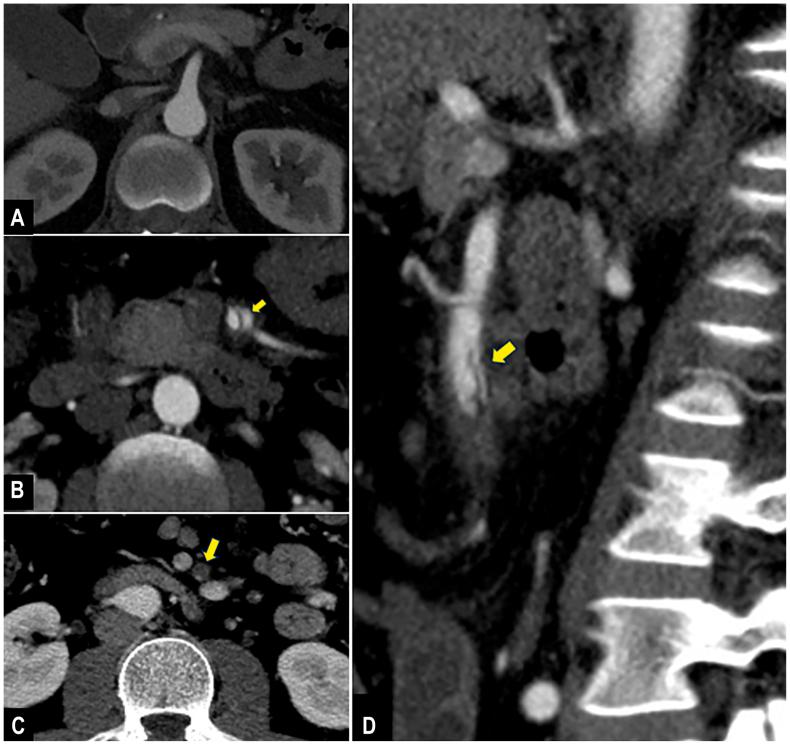

Isolated superior mesenteric artery dissection without aortic involvement is an exceptionally rare event. Nonoperative management remains the first-line therapy. However, surgical interventions can be indicated in the event of bowel ischemia. In the present report, we describe a case of complicated isolated superior mesenteric artery dissection treated with a hybrid approach.

孤立性肠系膜上动脉夹层且无主动脉受累是一种极其罕见的情况。非手术治疗仍然是一线治疗方法。然而,在出现肠缺血的情况下可能需要进行手术干预。在本报告中,我们描述了一例采用杂交手术方法治疗的复杂性孤立性肠系膜上动脉夹层病例。